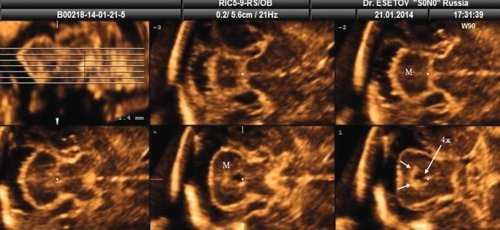

При изучении анатомии головного мозга плода в режиме 2D с применением стандартных аксиальных срезов во всех наших случаях мозжечок выглядел в виде овального образования однородной структуры с поперечным размером, менее уровня 5 процентиля для соответствующего срока беременности. При этом отсутствовала межполушарная выемка и область повышенной эхогенности по срединной линии мозжечка, характерная для отражения червя (рис. 1). На коронарном срезе также обращала внимание округлая однолобарная форма гипоэхогенного мозжечка (рис. 2). Использование трансвагинального подхода позволяло визуализировать дополнительно волокнистые структуры субарахноидального пространства (рис. 2).

Рис. 1. Аксиальные срезы головного мозга плода. Отражена картина однолобарного гипоплазированного мозжечка во всех наблюдениях.

а) Наблюдение 1.

б) Наблюдение 2.

в) Наблюдение 3.

г) Наблюдение 4.